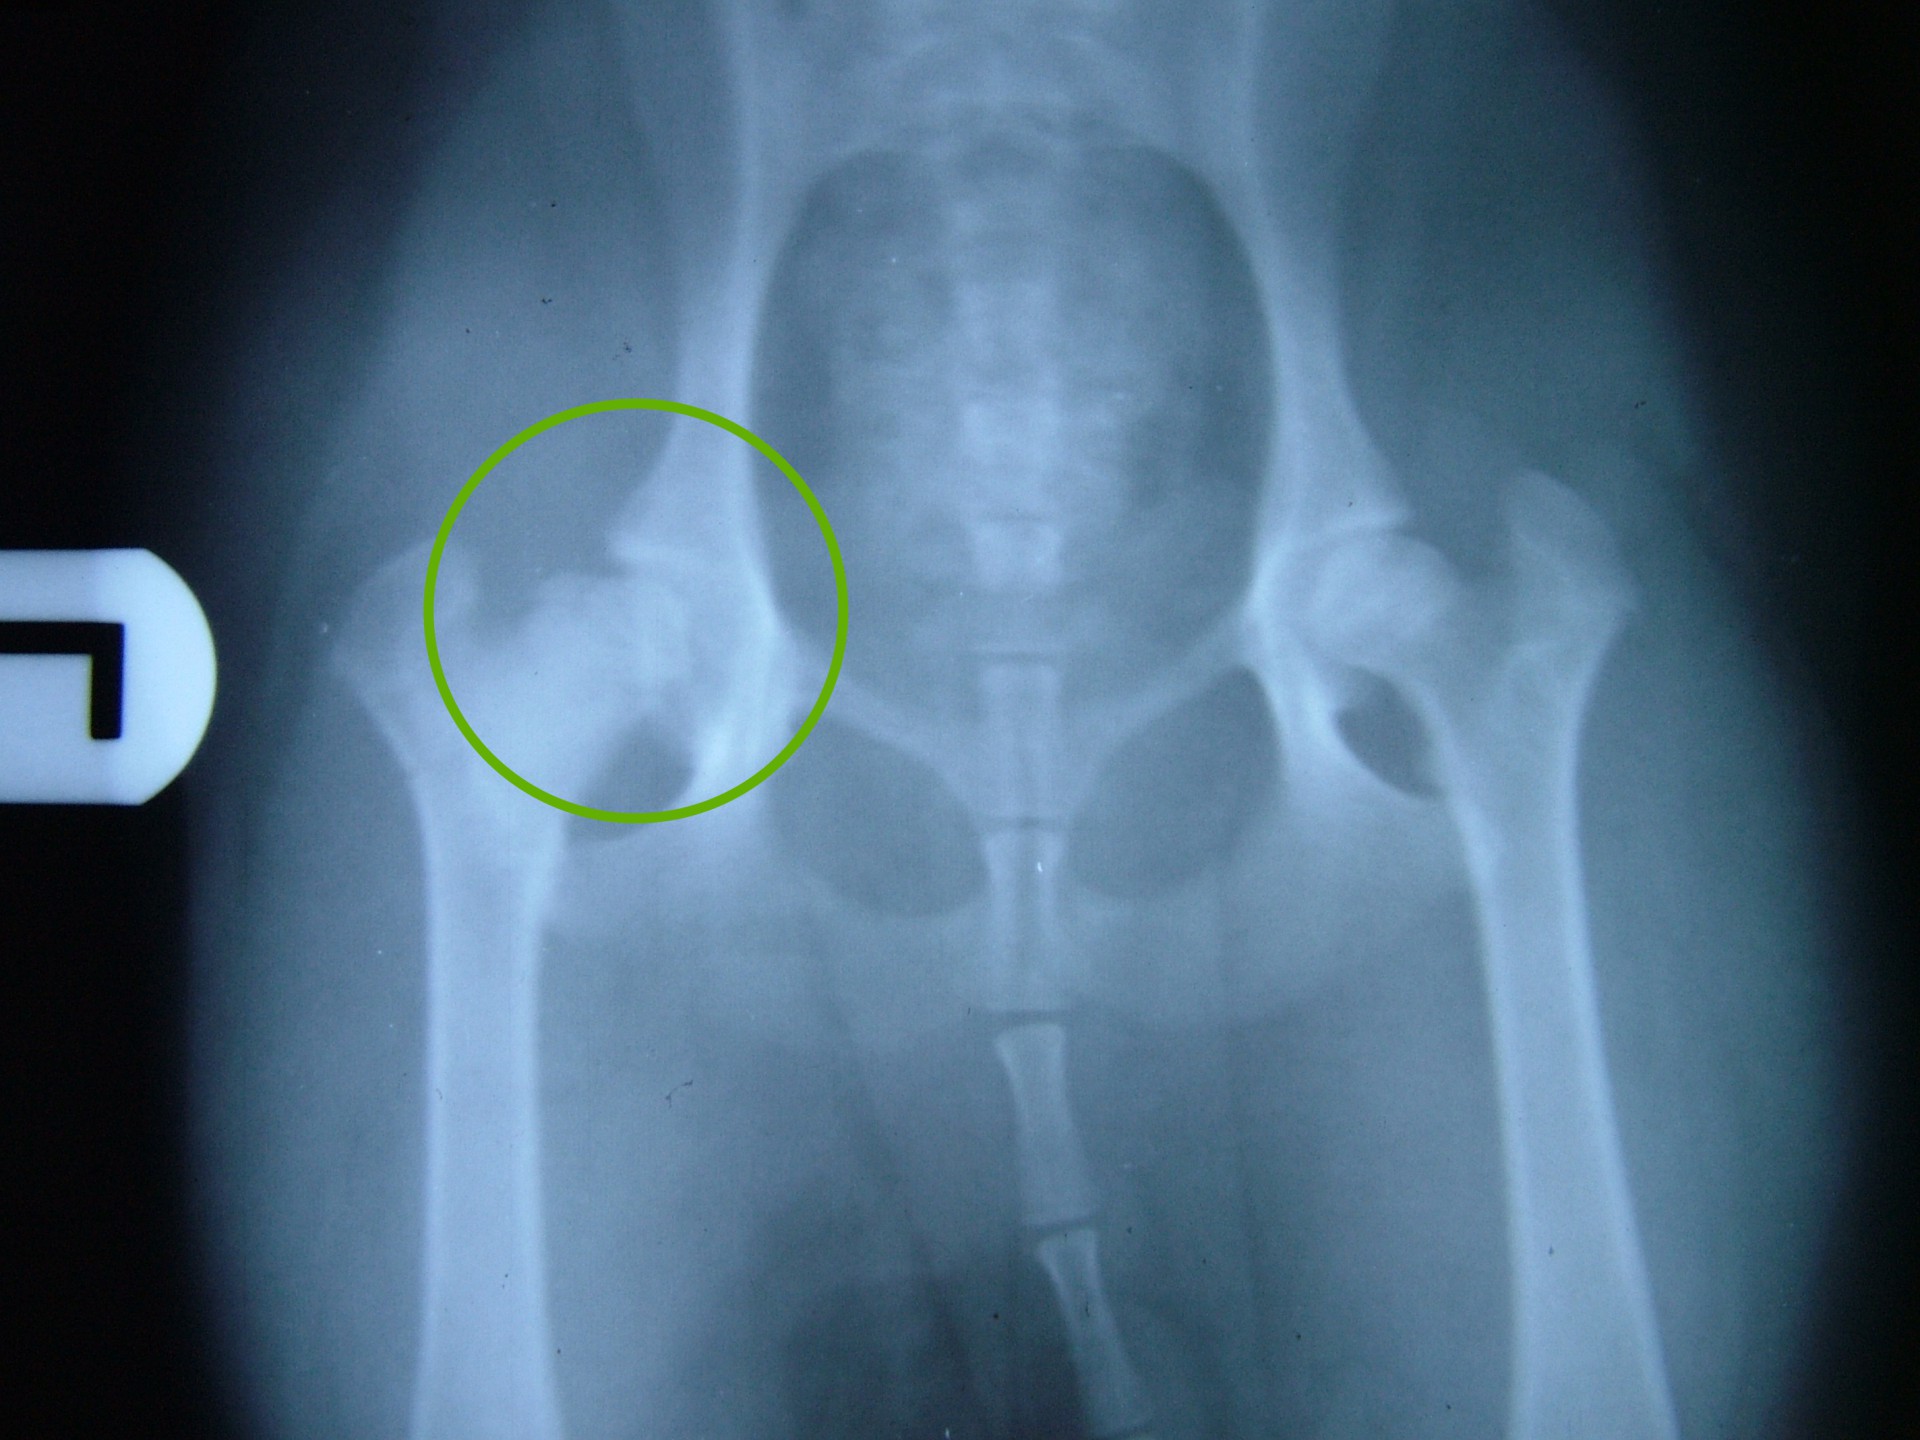

Ilyen esetben a 2-4 hét múlva elvégzett röntgen vizsgálat a Legg-Calve-Perthes kórt egyértelművé teszi.

A felvételen a combcsontfej csontos szerkezetének felbomlása, sok esetben a combcsontfej beroppanása látható.